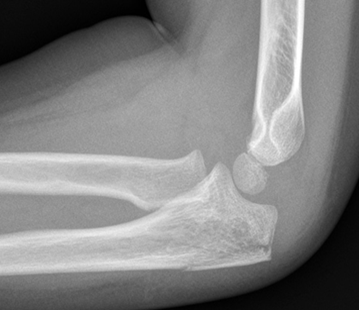

Olecranon fractures

- Olecranon fractures are often seen in combination with other elbow fractures (lateral condyle, supracondylar, radial neck or radial head dislocation).

Undisplaced olecranon fractures

- Above elbow plaster backslab at 90 degrees flexion with Orthopaedic Fracture clinic follow up in 7-10 days.

Displaced olecranon fractures

- Should be discussed with the Orthopaedic team for further management.

Non-displaced Olecranon fracture